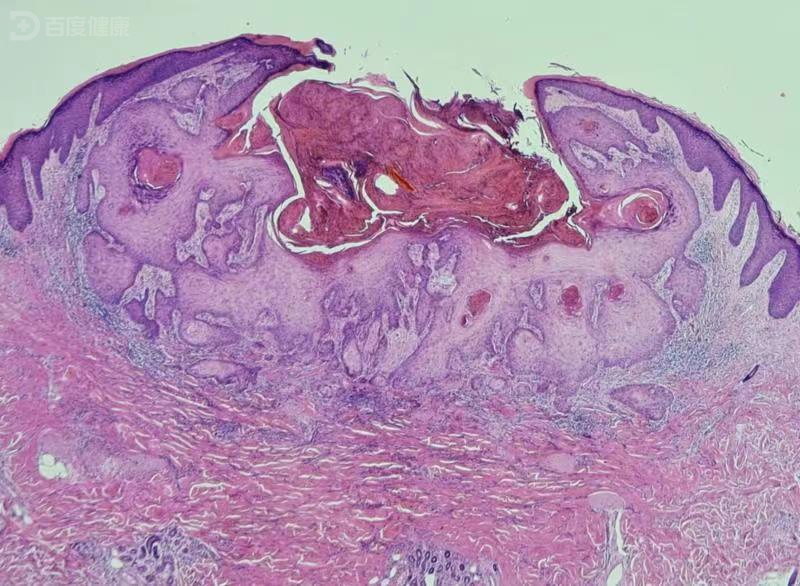

经典型角化棘皮瘤

角化棘皮瘤